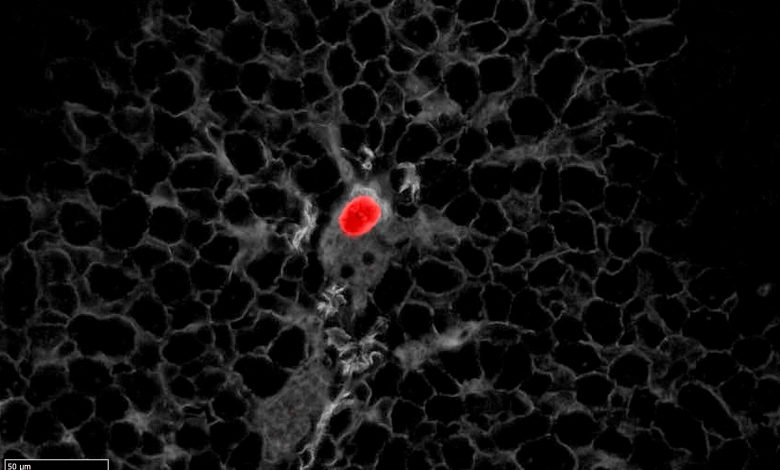

Organoides de câncer colorretal, editados para expressar um repórter tdTomato em células com alta expressão de proteína de membrana epitelial 1 (Emp1), foram implantados no ceco de camundongos para gerar tumores primários. Após várias semanas, seccionamos fígados inteiros e coramos para tdTomato (em vermelho) e E-Cadherin (cinza) para procurar células iniciadoras de metástases. Na foto, pode-se observar como as células tumorais em disseminação do CRC expressam altos níveis de Emp1, um gene marcador da população de células de alta recidiva (HRC) que descrevemos. Crédito: IRB Barcelona

Essas células têm pouca atividade proliferativa e não contribuem para o crescimento do tumor primário. No entanto, aglomerados de HRCs são capazes de se desprender do tumor principal, migrar para a corrente sanguínea, atingir o fígado e permanecer ocultos por algum tempo após a cirurgia. Em amostras de pacientes com câncer de cólon, os pesquisadores conseguiram verificar a presença dessas mesmas células naqueles indivíduos com maior risco de recaída após o tratamento.